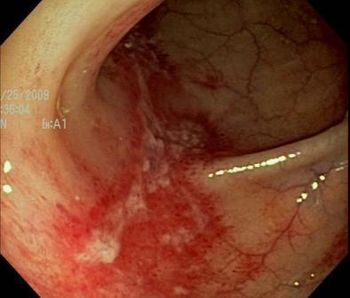

A 28-year-old man reports pain on swallowing of a week's duration. He is otherwise in good health. Upper endoscopy and tissue biopsy reveal the cause. What do you see?

The most frequently encountered cause of infection of the esophagus is Candida. Among viral causes HSV is the most common, followed by CMV.